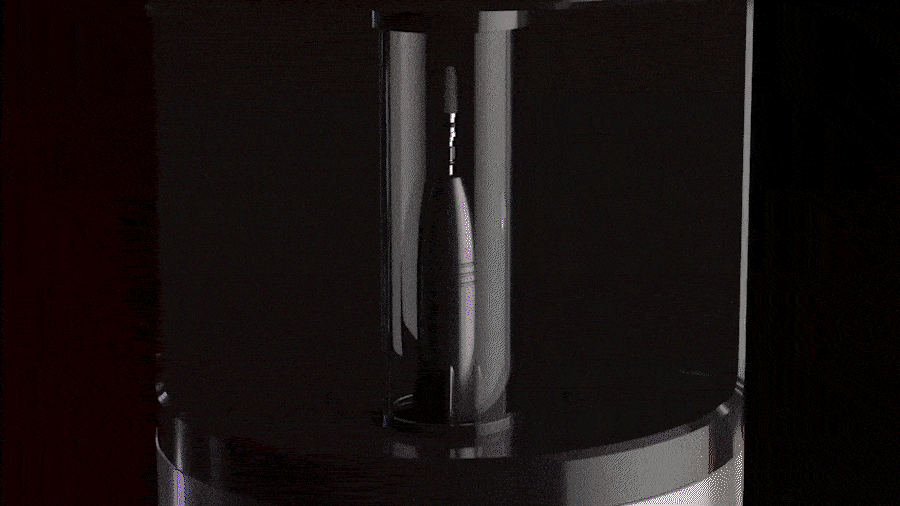

디지털 구강 스캐너

디지털 분석을 위해 CEREC PRIMESCAN

구강스캐너를 사용하여 정교하고 빠른 디지털

치과 진료가 가능합니다. 오차가 거의 없는

개인 맞춤 치료 계획을 수립합니다.

디지털 분석을 위해 구강 스캐너를 사용하여

정교하고 빠른 디지털 치과 진료가 가능합니다.

오차가 거의 없는 개인 맞춤 치료 계획을 세웁니다.